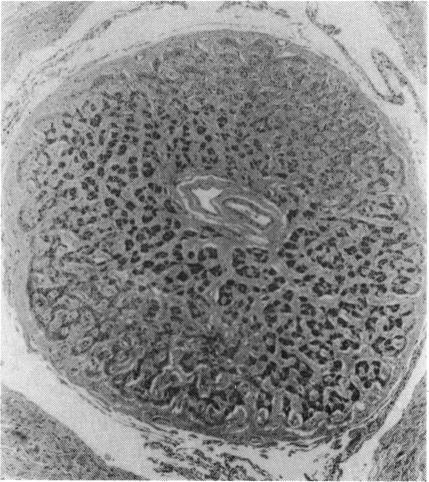

Two sibships, each with two affected males but no other affected family members, are described. All four patients at birth had small eyes with white masses visible behind clear lenses. Support for a diagnosis of Norrie's disease lies in the probable mental retardation and sudden death of one child and mental retardation in the other in one of the families, and strong support in the sensorineural deafness in one child in the other family. A necropsy was performed on the dead child. Both eyes showed the retinae to be totally non-attached. The optic nerves were thin. If the diagnosis is Norrie's disease (highly probable), the birth of the second affected child in each family supports the postulate of a mutation in the X chromosome of a germ cell of a maternal grandparent or an earlier maternal ancestor, no previous member of the family having been affected. That implies a 50% risk of the disease in future male siblings and a 50% risk of the carrier state in female sibs. When only one child is affected, the explanation could also be a mutation in that individual. Given Norrie's disease, we have calculated a mutation rate of 3.9 per million chromosomes in the Scottish population--remarkably similar to the mutation rates calculated for many dominant diseases. A diagnosis of autosomal recessive non-attachment of retina implies a 25% risk to later siblings.

本文描述了两个家系,每个家系中有两名患病男性,无其他患病家庭成员。所有四名患者出生时眼睛均较小,在透明晶状体后可见白色肿物。支持诺里病诊断的依据包括:其中一个家系中有一名儿童可能存在智力发育迟缓及猝死情况,另一名儿童存在智力发育迟缓;另一个家系中有一名儿童患有感音神经性耳聋,这为诊断提供了有力支持。对死亡儿童进行了尸检。双眼视网膜均完全脱离。视神经纤细。如果诊断为诺里病(极有可能),每个家系中第二名患病儿童的出生支持了这样一种假设:即 maternal grandparent(外祖父母中的一方)或更早的母系祖先的生殖细胞X染色体发生了突变,该家族中之前没有成员患病。这意味着未来男性同胞患病风险为50%,女性同胞成为携带者的风险为50%。当只有一名儿童患病时,也可能是该个体发生了突变。考虑到诺里病,我们计算出苏格兰人群中每百万条染色体的突变率为3.9——这与许多显性疾病计算出的突变率非常相似。诊断为常染色体隐性遗传性视网膜脱离意味着后续同胞有25%的患病风险。